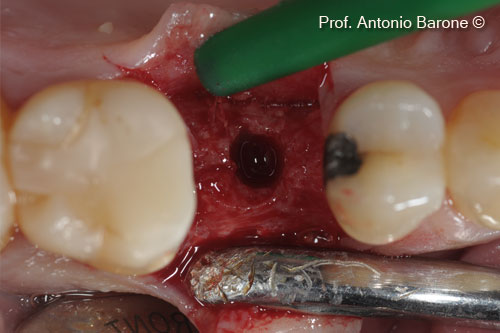

Hình ảnh lâm sàng của implant đã được cấy ghép. Đo độ dày xương mặt ngoài

Hình ảnh lâm sàn của các đường khâu